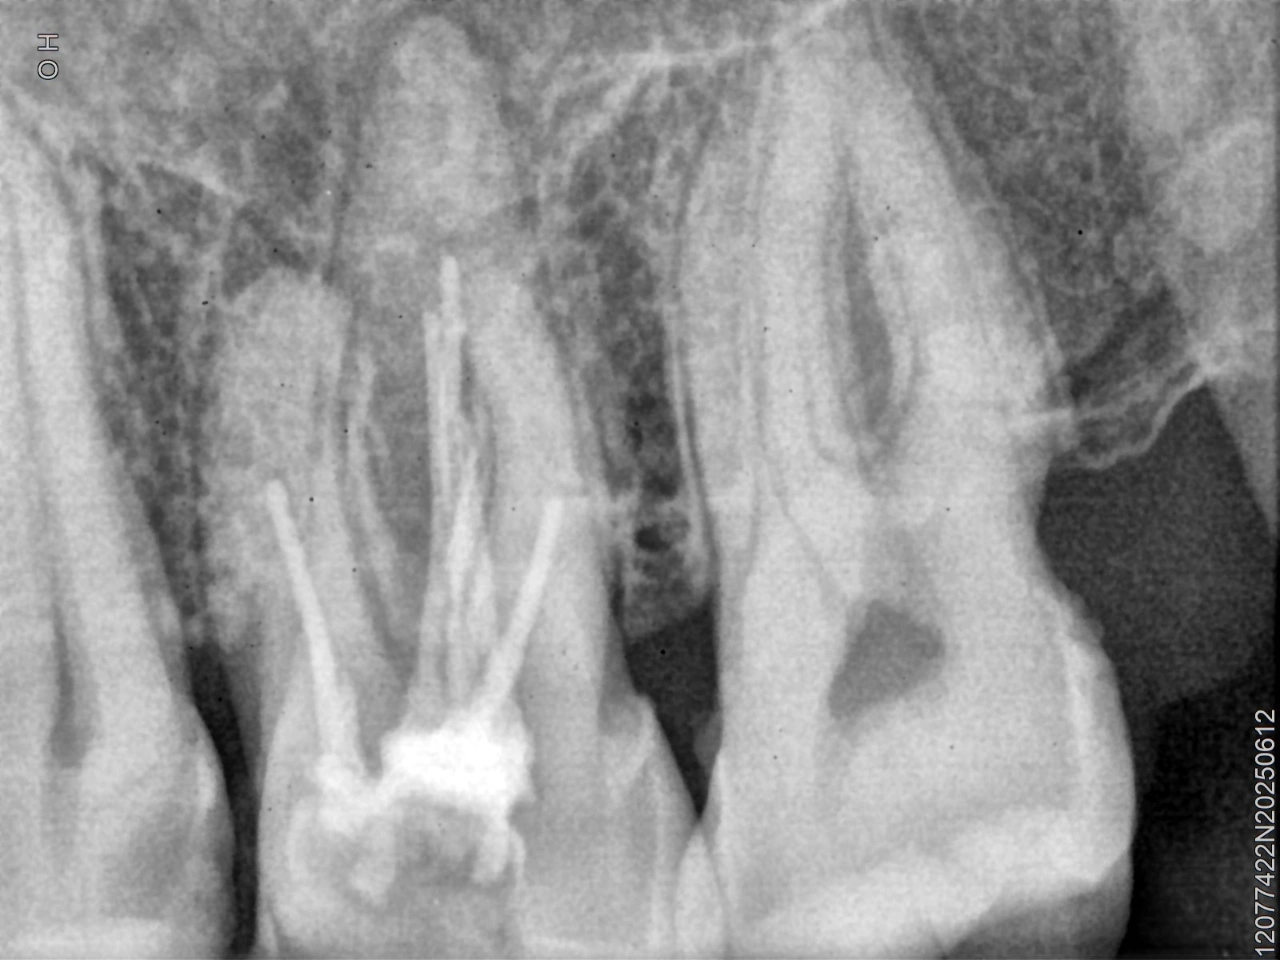

Clinical Cases